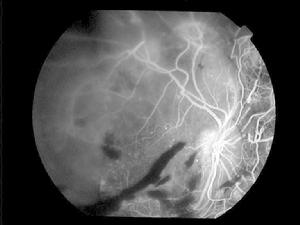

2.病人有不同程度的 視力下降和/或視物變形 。

3.眼底改變:視乳頭色淡、 水腫 ,邊界不清,視網膜血管明顯收縮,可呈銅絲狀或銀絲狀,高度收縮可使動脈不易辨認,經常可發現動靜脈交叉壓跡現象,視乳頭四周或整個視網膜 水腫 ;疾病進一步發展可出現視網膜棉絮狀滲出物與深度圓形或淺層火焰狀 出血 ;在黃斑區可呈典型的星芒狀滲出,嚴重的滲出,聚集於視網膜下可形成 視網膜脫離 。